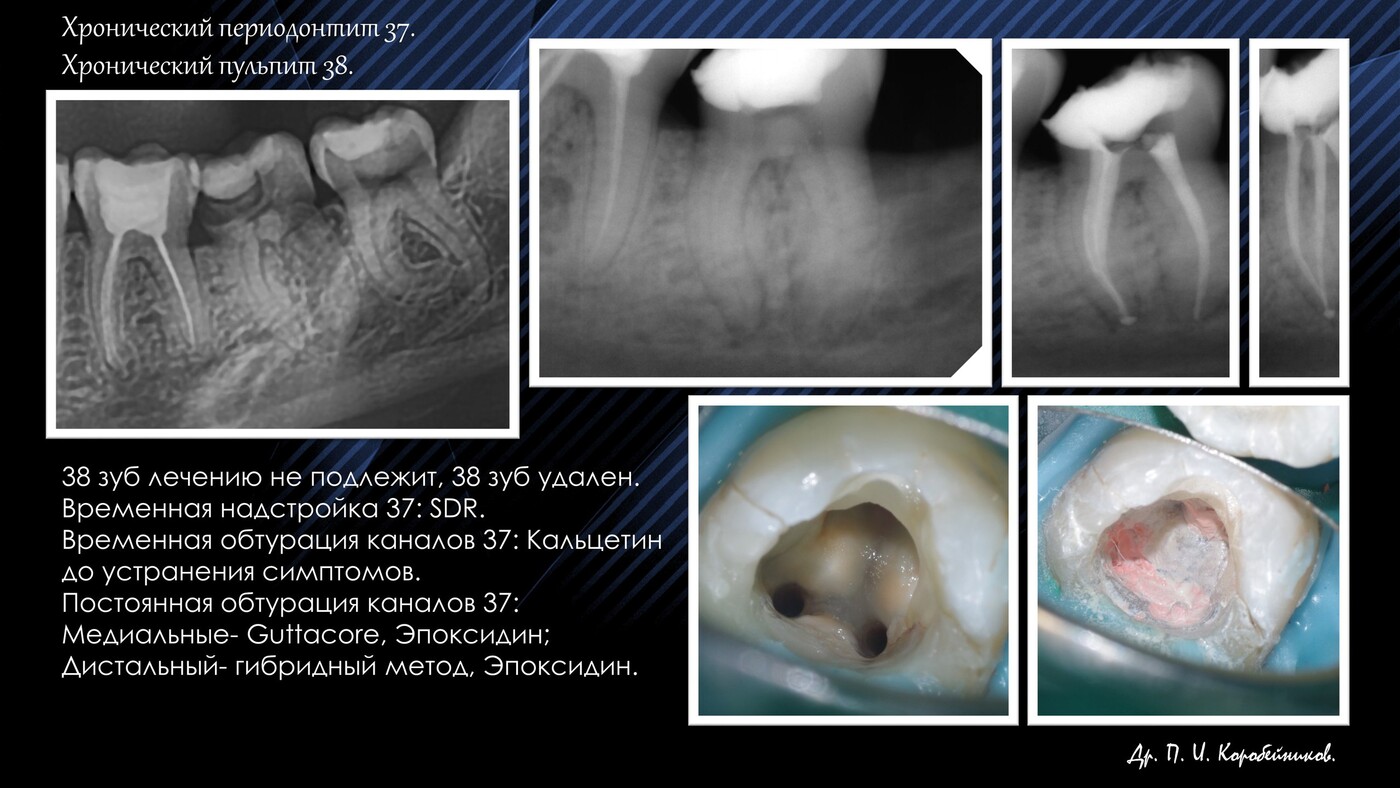

Стоматолог- эндодонт, стоматолог- терапевт, стоматолог- ортопед, стоматолог- хирург.

Работа с микроскопом, консультации и лечение пациентов, эндодонтия, терапия, ортопедия, хирургия(в небольшом объеме).